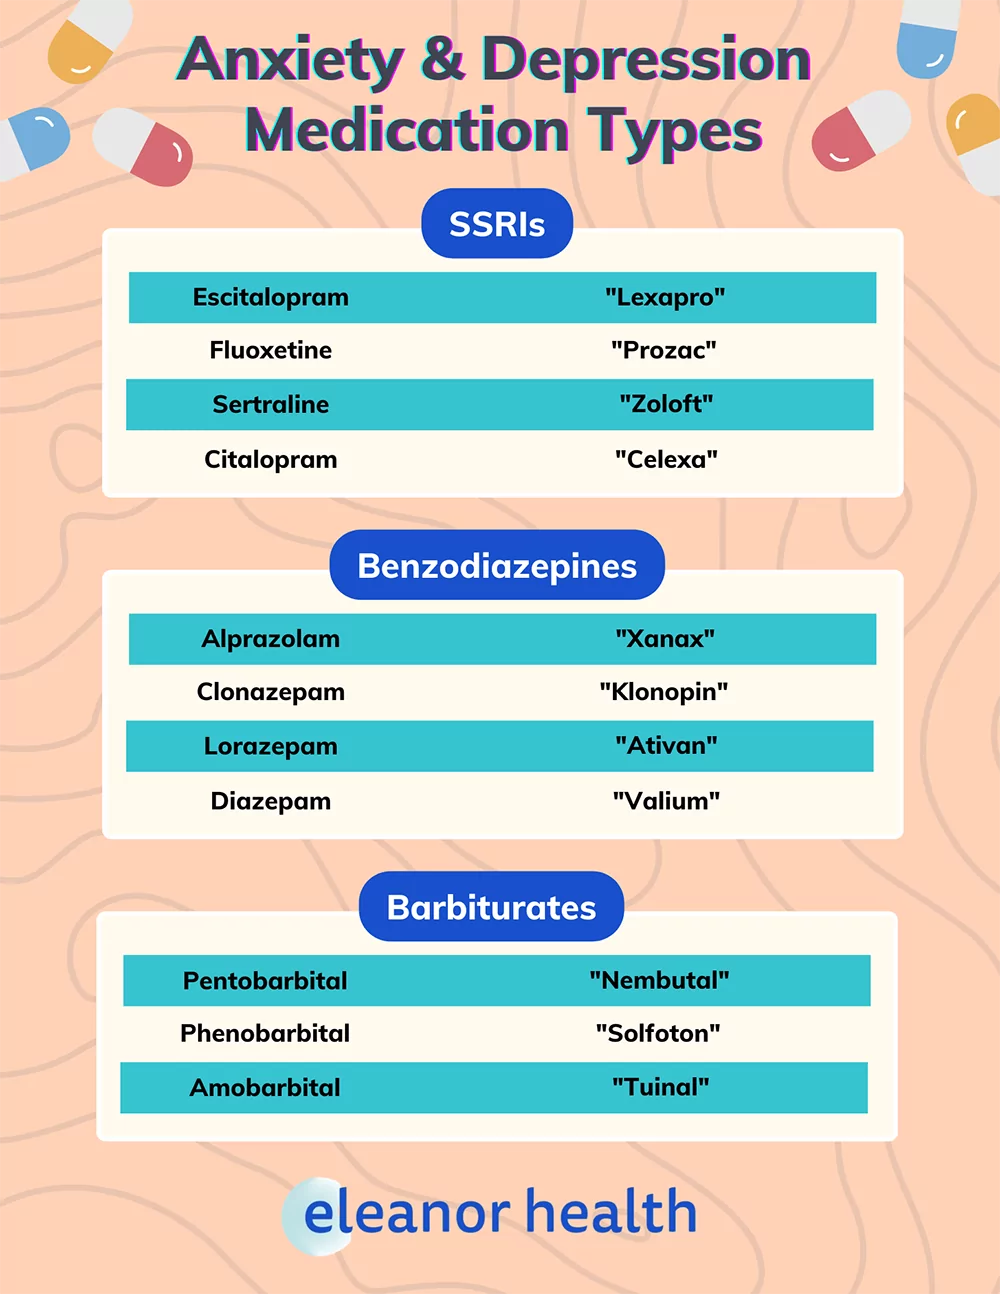

Depression Medication Brands

Cardiac Medications By Order Of Priority In My ABCCDE Process From My